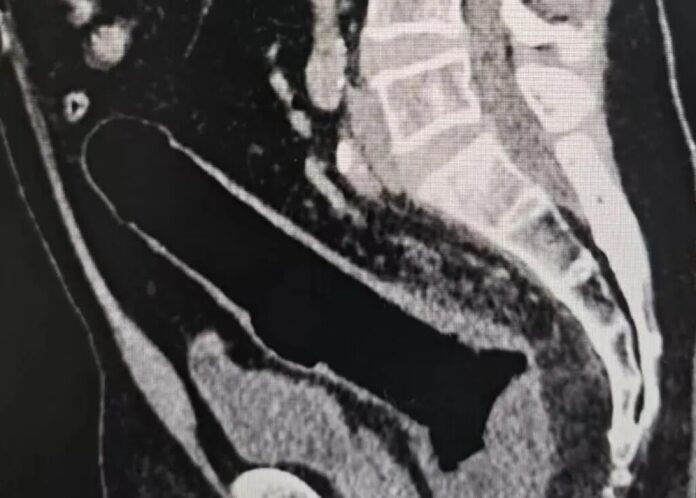

誰知兩三天過去,異物不僅沒有排出,患者還出現了明顯腹痛。再次就醫做斷層掃瞄檢查後,結果顯示腸道已經穿孔,原本簡單的異物取出問題,徹底演變成了急症。

翻攝自網路